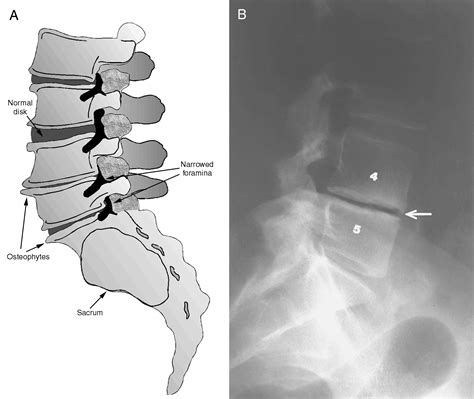

The Posterior Disc Osteophyte Complex refers to the formation of bone spurs (osteophytes) on the posterior aspect of the vertebral bodies, often in conjunction with degenerative disc disease. This condition is characterized by the growth of bony projections that can impinge on spinal nerves, leading to pain, numbness, and weakness. PDOC is a common finding in patients with chronic back pain and is often diagnosed through imaging studies such as X-rays, CT scans, or MRI.

• Imaging Studies: Various imaging techniques are used to visualize the spine and identify the presence of osteophytes. These may include:

X-rays Provide a basic view of the spine and can detect bone spurs and other abnormalities.

CT Scans Offer detailed images of the bony structures and can help identify the location and size of osteophytes.